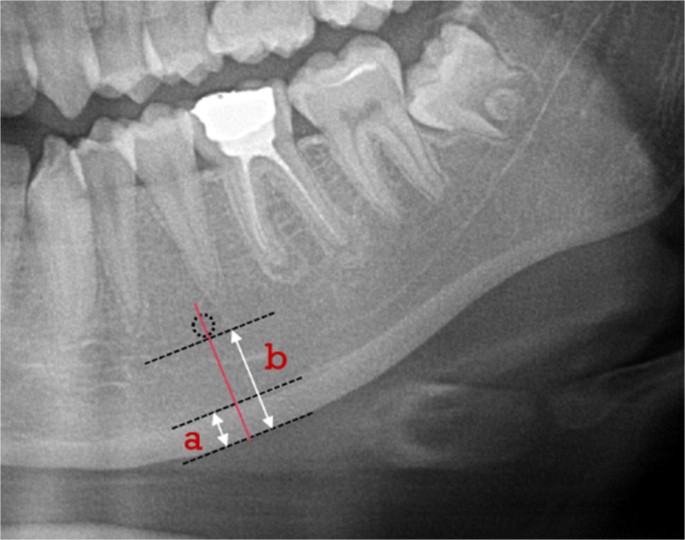

Panoramic radiograph reveals mandibular cortical width and other... | Download Scientific Diagram

Mandibular cortical width measurement (MCW). ( A ) Graphic... | Download Scientific Diagram